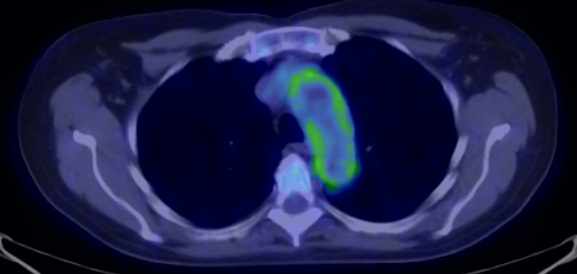

The most common clinical use of FDG-PET is in the form of whole-body scan, with oncologic indications. The majority of malignant tumors operate with higher energy consumption and show an increased glucose metabolism, consequently an increased uptake of FDG. The grade of malignancy is usually proportional to the rate of uptake. This method is useful in oncologic diagnostics, since it is capable to differentiate benign lesions from malignant ones. Whole-body PET imaging is capable to detect the primary tumor with local nodal metastases as well as distant metastatic lesions (staging) in one examination. (Figure 10.)

Test iframe

a

Image

b

c

d

10. Ewing’s sarcoma in the right humerus. Staging FDG PET-CT. PET Maximum Intensity Projection (MIP) image (a), transversal (b,c) and coronal (d) plane fused PET-CT images. Multiplex metastatic process with nodal, lung and bone involvement.